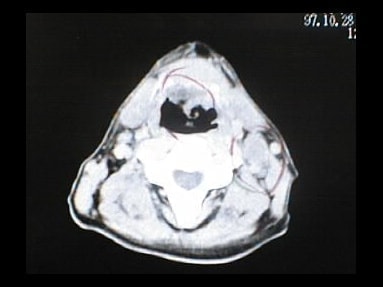

CT画像比較

中咽頭末期がんCT画像①

入院当時CT画像①

中咽頭末期がん消滅CT画像①

入院3か月後癌消滅CT画像①